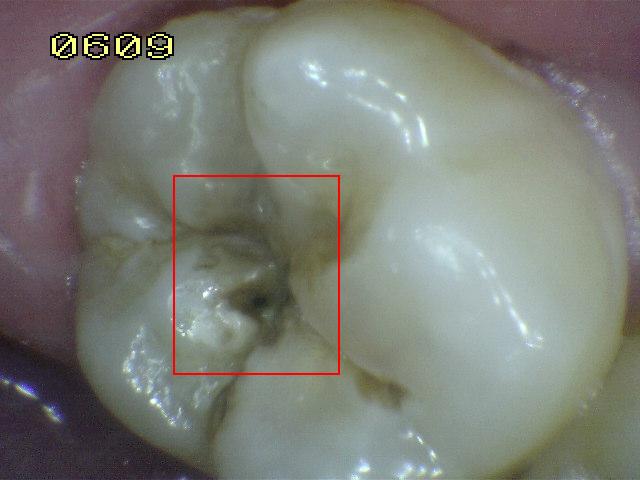

Código 5:

Cavidad detectable con dentina visible hasta la

mitad de la superficie

- Hay una cavidad en el esmalte opaco

o decolorado, dejando al descubierto la dentina. El diente

visto en estado húmedo puede haber oscurecimiento de la

dentina visible a través del esmalte. Una vez seco, hay

evidencia visual de la pérdida de la estructura del diente a la

entrada o dentro de la fosa o fisura, cavitación franca

> 0,5 mm hasta la mitad de la superficie dental. Hay evidencia visual de

desmineralización ( blanco opaco, de color marrón o paredes negras

ó de color marrón) en la entrada o dentro de la fosa o fisura. A juicio

del examinador se observa dentina expuesta en el piso y paredes de la

cavidad.